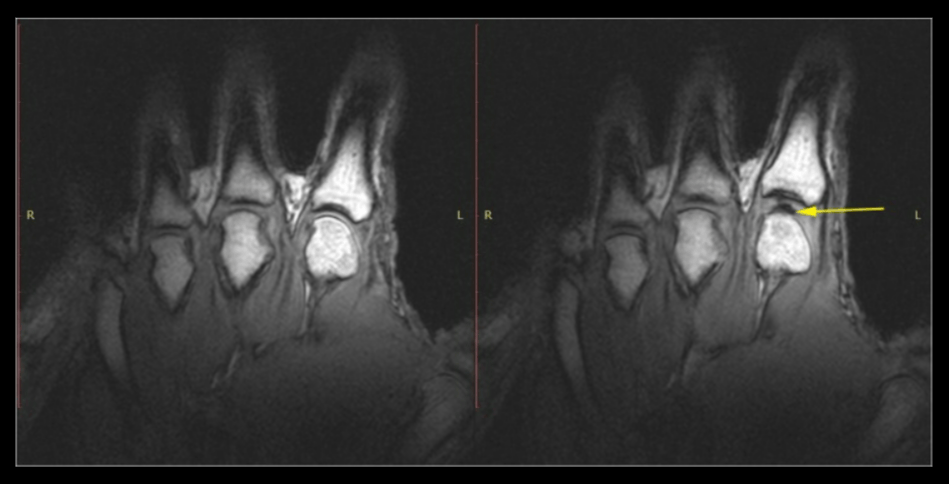

Слева: рука в покое перед растрескиванием. Справа: та же рука после хруста от растяжения. Обратите внимание на тёмную межсуставную полость (жёлтая стрелка). Источник изображения: pubmed.ncbi.nlm.nih.gov